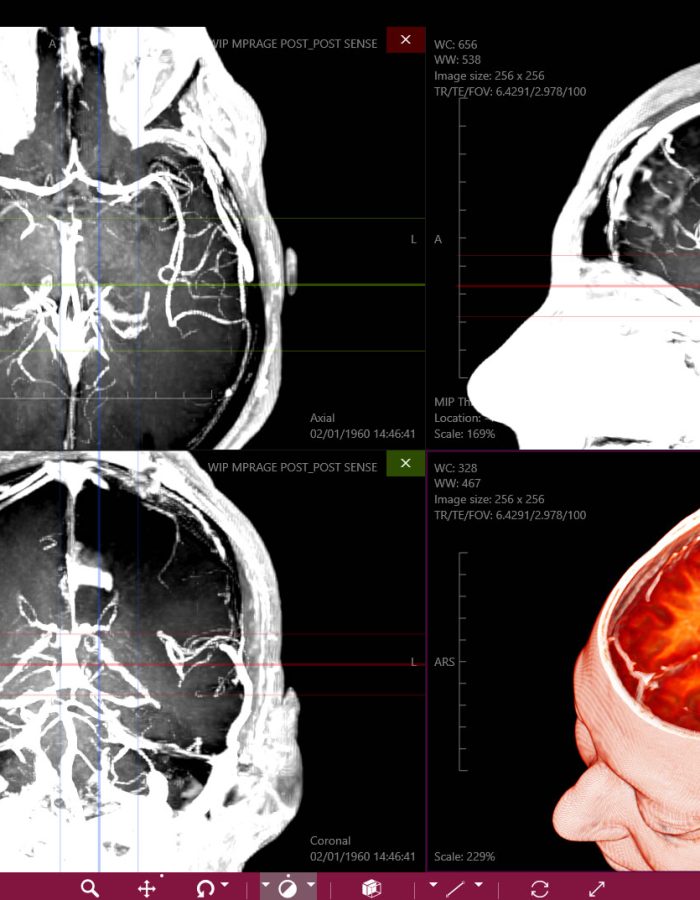

_ Amplia variedad de imágenes con un estilo profesional, tanto para estudios de casos pre operatorios como para estudio profundo de medicina.